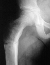

The patient demonstrated a large pigmented lesion with irregular border located in the right upper back. There was a two centimeter leg length discrepancy by the block test. X-rays showed an expansile radiolucent area with a ground glass density involving the right proximal femur . There was a healing transverse subtrochanteric fracture involving the lateral cortex . There was also an expansile lesion noted in the midshaft of the right fibula . A scanogram revealed a 1. 8 cm leg length discrepancy with right leg shorter than left . Bone age was 14 years old ( 4 years advanced) .

1. Fibrous dysplasia-pain, pathologic fracture, limp or deformity, of the 'involved bone. Most common deformity is varus of the proximal femur-"Shepherd's Crook deformity".

Fibrous dysplasia is an intramedullary diaphyseal /metaphyseal lesion that blends with a thinned, slightly bulged cortex. The cortex of the affected bone may be thinned by endosteal erosion which creates a scalloped pattern. In long bones, the lesions are usually metaphyseal in location, extending into the rnid-diaphysis. The lesion has a homogenesis density @g it a so-called "ground glass" appearance. An angular deformity in the bone is often present at the level of the lesion. Periosteal reaction is absent except when a pathologic fracture is present. Bone scans show increased uptake-can assess the extent and multiplicity of involvement. CT scan is helpful in differentiating eosinophilic granuloma, osteomyelitis, and unicameral bone cyst. These show lower Hounsfield units (O to 40), compared to fibrous dysplasia (70 to 130). Few studies other than plain X-rays are required in a typical case of polyostotic disease.